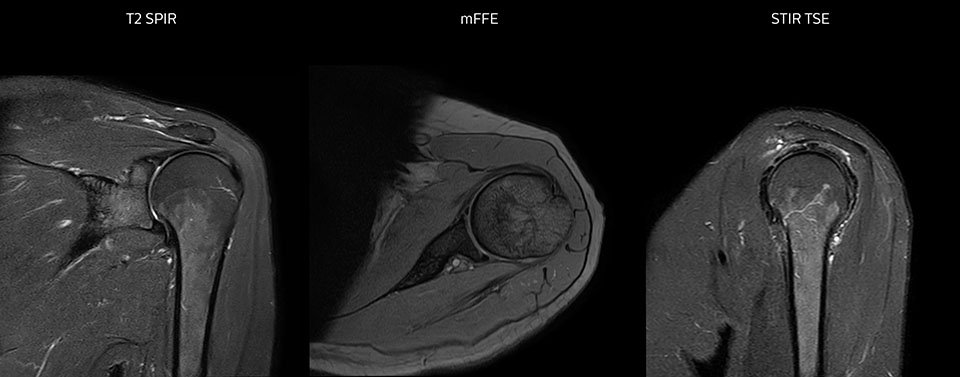

The Prodiva shoulder coil is very flexible and has large coverage, which makes good positioning easier, and that contributes to the superb image quality and high SNR that we get in our shoulder exams.

Scan time 2:55 min, FOV 160 mm, acq voxels 0.55 x 0.83 x 3.0 mm.

Scan time 4:19 min, FOV 160 mm, acq voxels 0.55 x 0.80 x 3.0 mm.

Scan time 2:50 min, FOV 160 mm, acq voxels 0.70 x 0.99 x 3.0 mm.